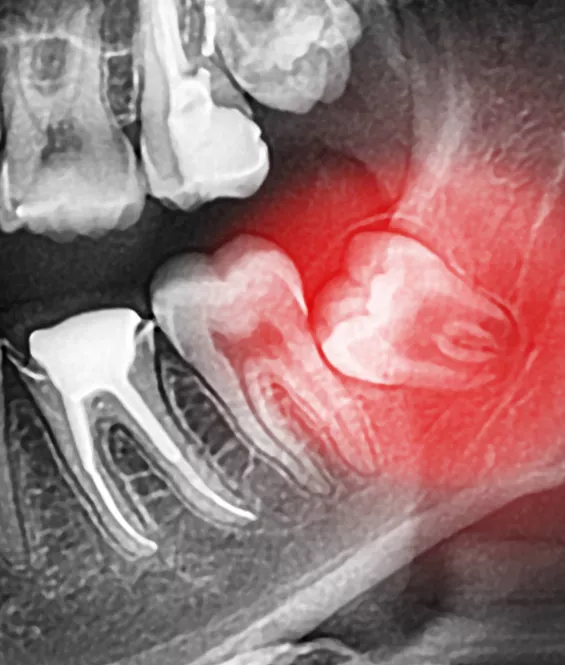

wisdom teeth xray

The wisdom teeth are a third set of large molars. They are usually the last of the adult teeth to grow in. For many patients, there is no room in the jaw for the wisdom teeth to emerge correctly, and they can become impacted or misaligned. If we detect that this is happening, we will recommend extraction of the wisdom teeth before they erupt through the gums.

Because the wisdom teeth are usually removed before they erupt, removal is usually a surgical procedure where the teeth are removed through incisions in the gums. The procedure is usually performed under local anesthetic and mild sedation. After the procedure, the incisions are closed with sutures.